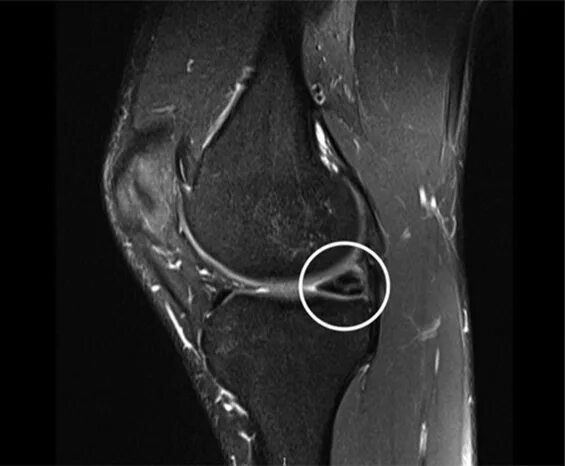

Повреждение латерального мениска 3